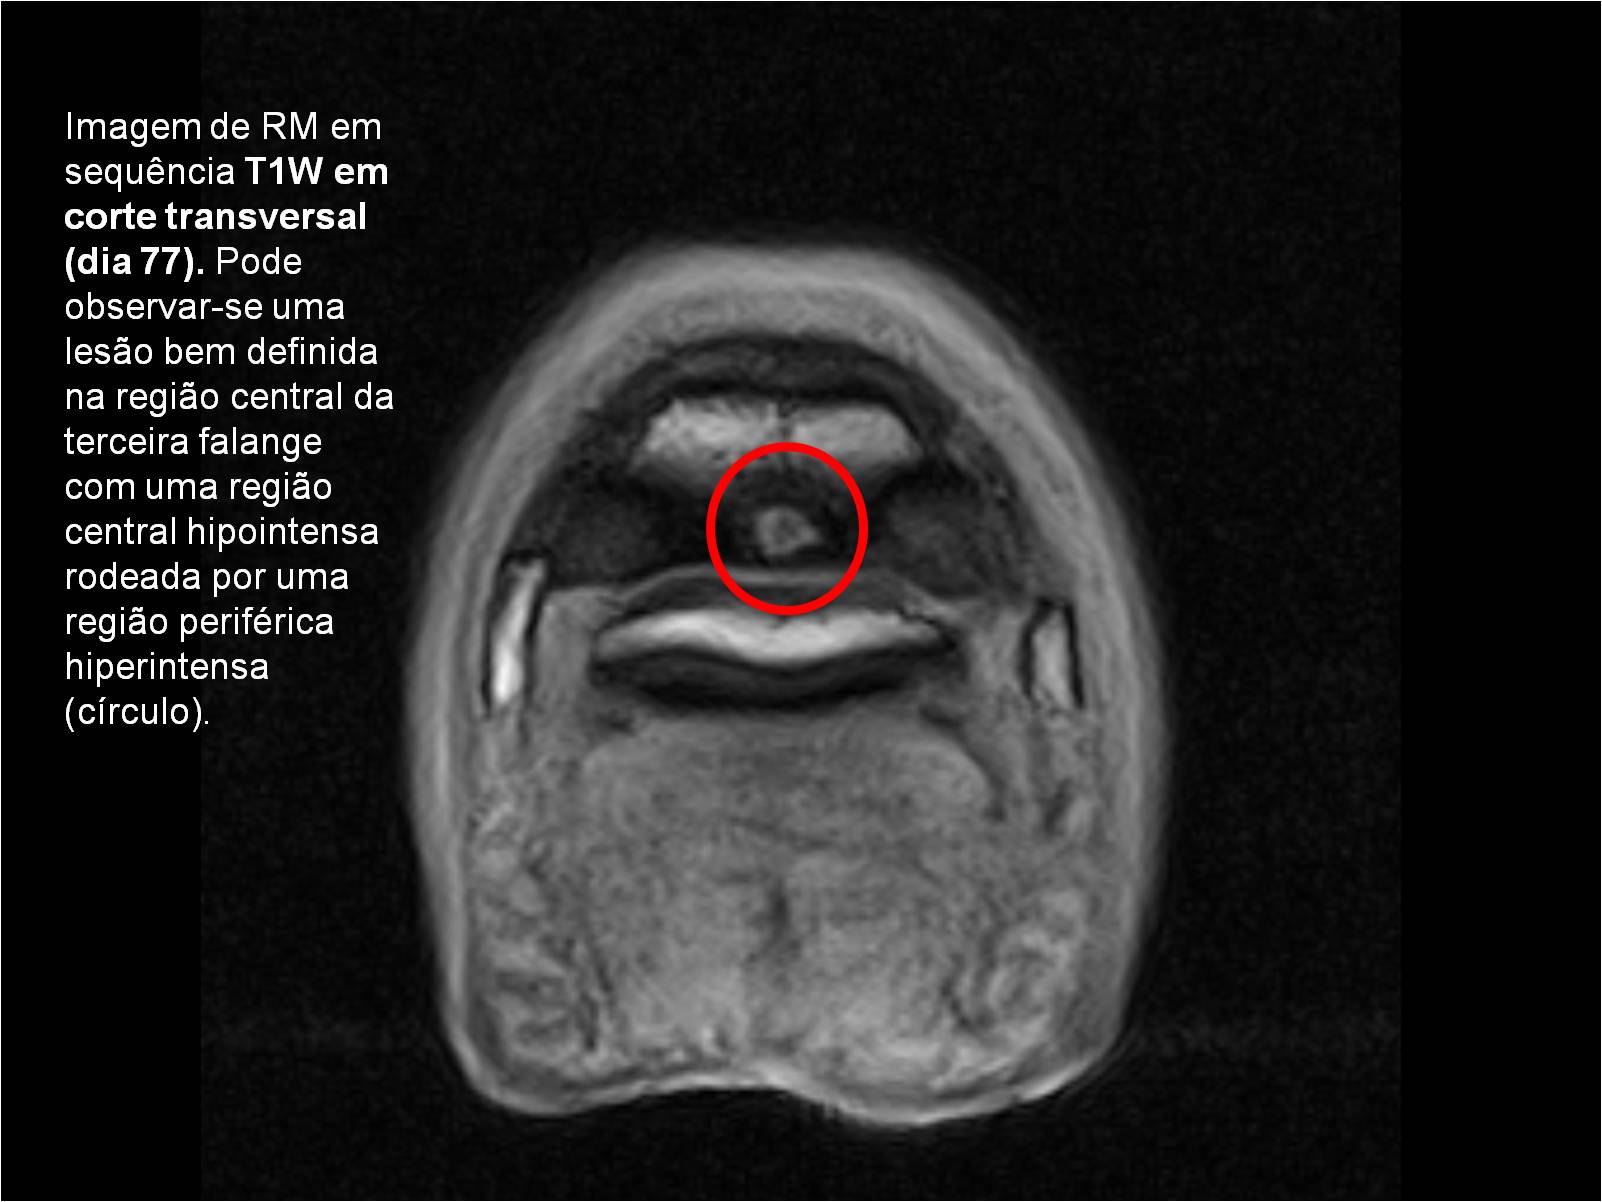

Publisher: Universidade de Évora

Abstract: O relatório de estágio encontra-se estruturado em três partes distintas. A primeira parte faz a caracterização das infraestruturas e funcionamento do Hospital Veterinário de Equinos de Lüsche, Oldenburg, Alemanha, assim como a análise casuística dos casos clínicos acompanhados durante os 6 meses de estágio. A segunda parte consiste de uma revisão bibliográfica sobre quistos do osso subcondral em equinos. Por fim, a terceira parte consta da apresentação e discussão de um caso clínico, nomeadamente o diagnóstico e acompanhamento imagiológico, por ressonância magnética, de um quisto subcondral na terceira falange num cavalo adulto; ### Abstract Equine Practice- Subcondral bone cyst of the third phalanx This internship report is divided in three parts. The first part characterizes the infrastructure and function of the Equine Hospital Lüsche, Oldenburg, Germany, as well as the casuistic of the clinical cases accompanied during the 6 month internship. The second part consists in a bibliographic review of cystic lesions of the subchondral bone in equines. The third part consists in a case report, the diagnostic and imagiological accompaniment, by use of magnetic resonance imaging, of a subchondral bone cyst in the distal phalanx of an adult equine.